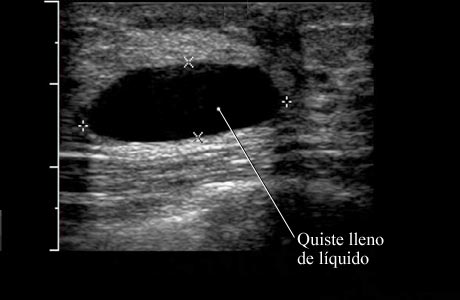

Imagen de un quiste simple de seno

Cortesía de Intermountain Medical Imaging, Boise, Idaho.

Esta imagen de la ecografía muestra un quiste simple rodeado de tejido mamario normal. Debido a que este tipo de quiste por lo general no contiene ningún tejido ni otra partícula, su médico sabe que está lleno de líquido y que puede drenarse si es necesario.